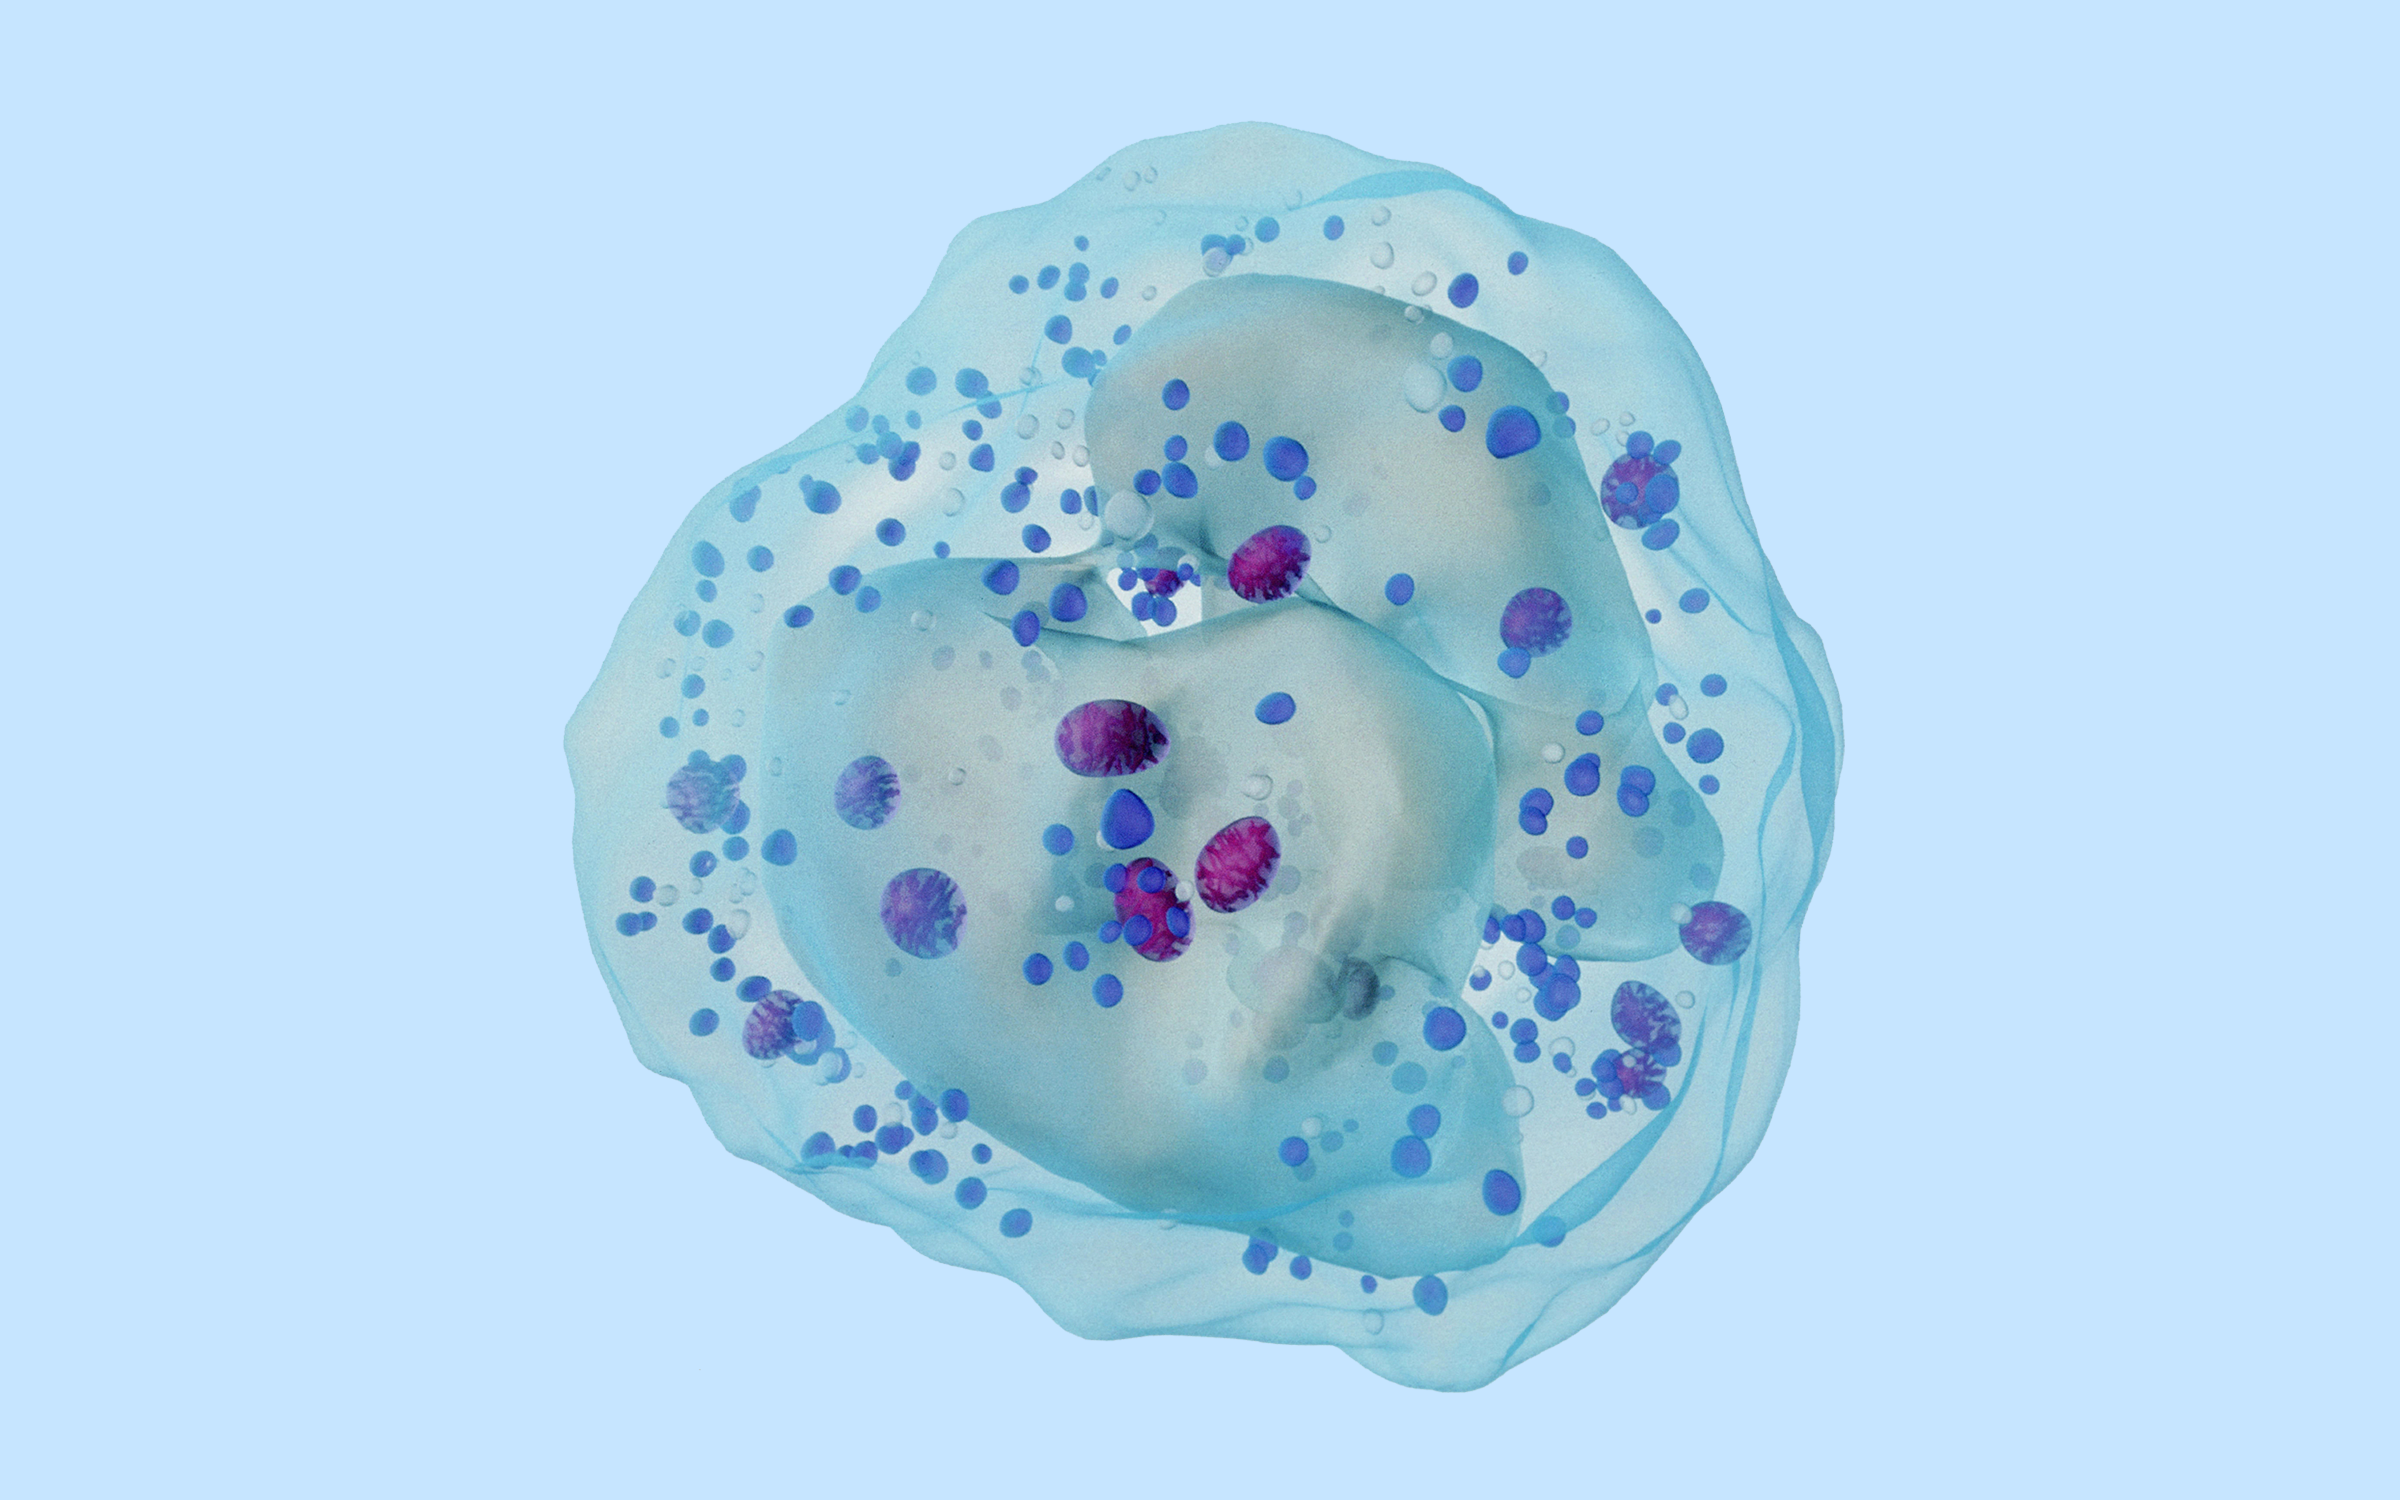

招募复发或难治性非霍奇金淋巴瘤患者 | 靶向CD20的CAR-T细胞

进行中一项评价U16注射液治疗难治/复发B细胞非霍奇金淋巴瘤(r/r B-NHL)的安全性和有效性的单臂、开放性、多中心的I/II期临床研究